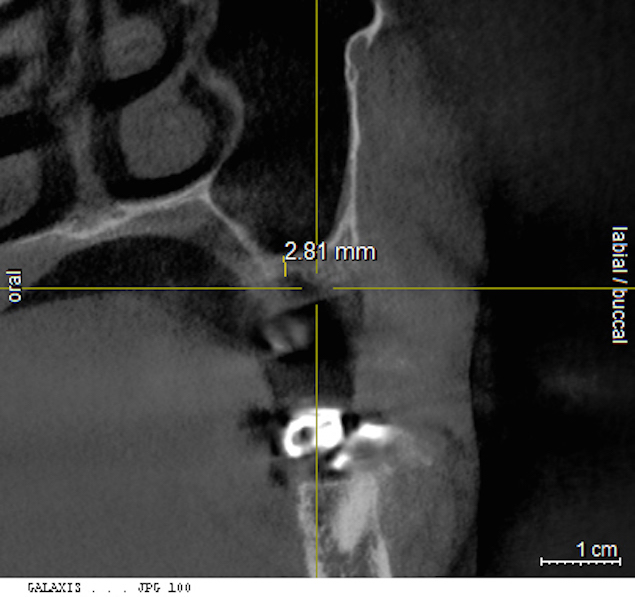

Cross-sectional view of the edentulous site demonstrating minimal bone height below the sinus floor.

Figure 22